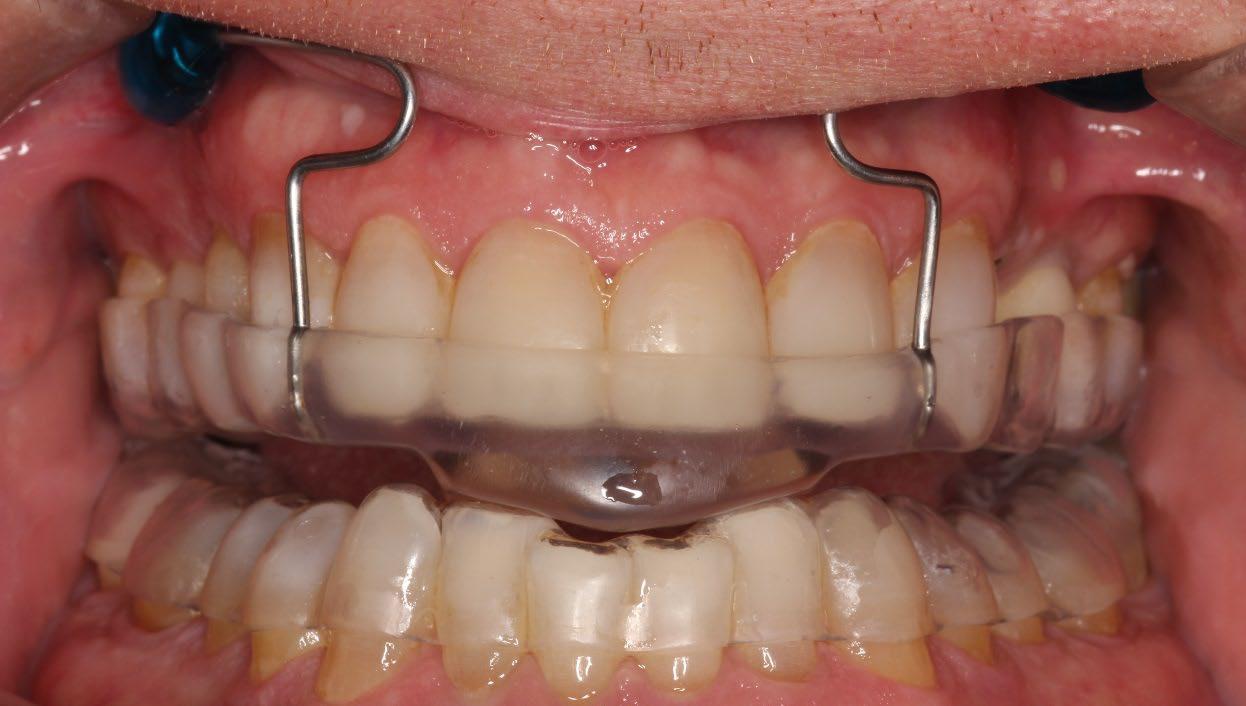

Consider non-custom appliances

• Temporary device to predict patient compliance, efficacy, position

• Interim device if custom is lost, damaged

Non-custom appliance

Levine et al. 2022 * 485